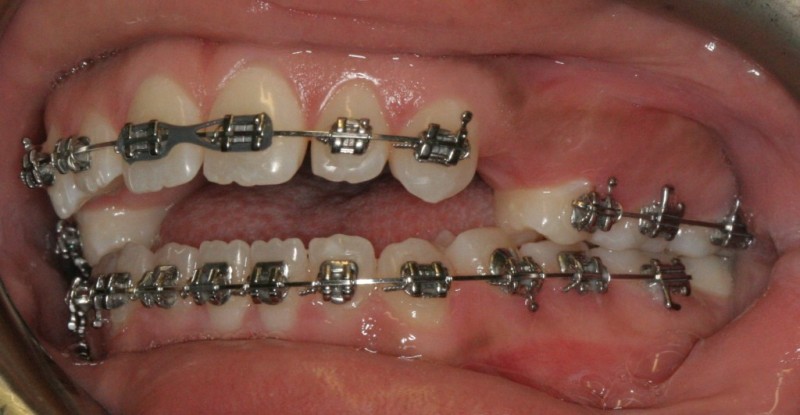

Case from Start to Finish

Pretreatment - Patient on Presentation

After Orthodontic Setup - Presurgical